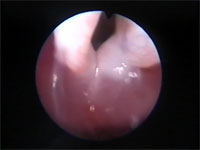

Abb 1 Kehlkopf-offen

Abbildung 1: Larynx der Katze. Rima glottidis (oben) und Plica vocalis sind geöffnet.

Der Larynx funktioniert wie eine Klappe zwischen den oberen und unteren Atemwegen. Seine wichtigsten Funktionen sind der Schutz der unteren Atemwege vor der Inhalation von Fremdkörpern, die Kontrolle des Atemwegdurchmessers während des Atmungszyklus und die Stimmbildung. Die Kehlkopftasche (Ventriculus laryngis) fehlt bei der Katze. Dorsal der Processi cuneiformes der beiden Aryknorpel befindet sich eine bei der Katze eine kleine schmal ovale Öffnung, die als Stimmritze (Rima glottidis) bezeichnet wird. Der Durchmesser der Stimmritze wird durch die Lage und Länge der Stimmfalten bestimmt, die wiederum von der Lage der Aryknorpel abhängen. Eine dorsolaterale Bewegung der Aryknorpel zieht die Stimmfalten auseinander und sorgt damit für eine Erweiterung der Stimmritze. Eine mediane Bewegung führt zu einer Verengung der Stimmritze bis auf eine schlitzartige Öffnung oder zu deren vollständigem Verschluss.